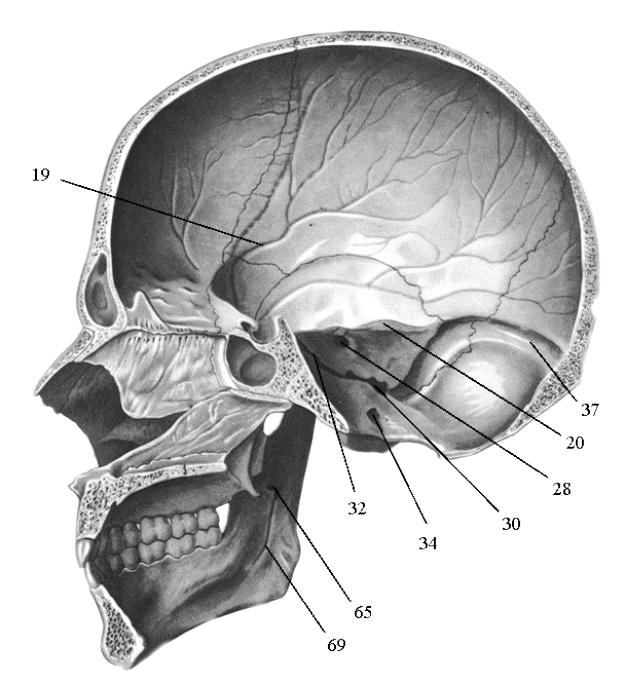

Анатомические детали: Фотографии топографии черепа с нижнего вида

Раздел: Альбом идей